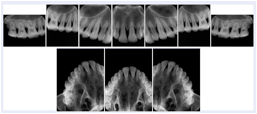

Intra-oral radiography typically involves acquisition of multiple images of various parts of the dentition. Many digital radiographic systems offer customized templates that are used for displaying the images in a study on the screen. These templates may also be referred to as mounts or view sets. The Structured Display Object represents a standard method of encoding and exchanging the layout and intended display of Structured Displays. A structured display object created in this manner could be stored with a study and exchanged with images to allow for complete reproduction of the original exam.

1. A patient visits a General Dentist where a Full Mouth Series Exam with 18 images is acquired. The dentist observes severe bone loss and refers the patient to a Periodontist. The 18 images from the Full Mouth Series along with a Structured Display are copied to a DICOM Interchange CD and sent with the patient to see the specialist. The Periodontist uses the CD to open the exam in his Dental Radiographic Software and consults via phone with the General Dentist. Both are able to observe the same exam showing the images on each user's display using the exact same layout.

Intra-oral Full Mouth Series Structured Display

Figure OO-1. Intra-oral Full Mouth Series Structured Display